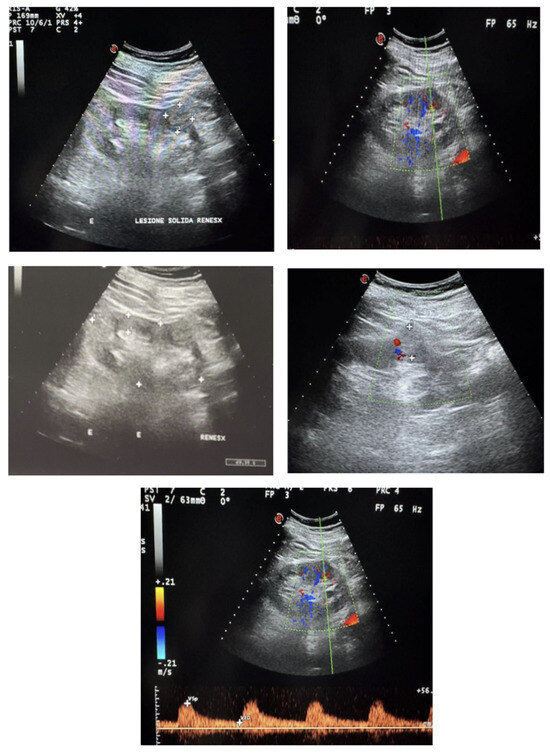

Isoechoic Renal Tumors: A Case Report and Literature Review

by Nicola Sinatra, Giulio Geraci, Roberto Palumbo, Gaspare Oddo, Giuseppe Zichittella, Emanuele Cirafici, Alessandra Sorce, Giuseppe Mulè and Caterina Carollo

Background and Clinical Significance: Isoechoic renal tumors, defined as masses demonstrating echogenicity similar to normal renal parenchyma, represent a significant diagnostic challenge in contemporary ultrasonographic practice. These lesions, occurring in 5–12% of all renal masses, frequently escape detection on conventional ultrasound, leading [...] Read more.

Background and Clinical Significance: Isoechoic renal tumors, defined as masses demonstrating echogenicity similar to normal renal parenchyma, represent a significant diagnostic challenge in contemporary ultrasonographic practice. These lesions, occurring in 5–12% of all renal masses, frequently escape detection on conventional ultrasound, leading to delayed diagnosis and potentially adverse oncological outcomes. Isoechoic renal tumors encompass both benign and malignant entities, with clear cell renal cell carcinoma representing 65–70% of malignant cases. Conventional ultrasound shows limited sensitivity (48–67%) for detecting isoechoic masses, while contrast-enhanced ultrasound achieves detection rates of 94–98%. Multiparametric MRI and dual-energy CT provide superior characterization, with accuracy rates of 85–92% for differentiating benign from malignant lesions. Case Presentation: We describe the case of an 80-year-old male in whom a 2.4 cm isoechoic renal mass was incidentally detected during abdominal ultrasound performed for chronic kidney disease monitoring. Contrast-enhanced CT confirmed a solid, hypervascular lesion with wash-out characteristics. Given the patient’s age, comorbidities, and tumor characteristics, multidisciplinary evaluation led to an active surveillance strategy. At 6-month follow-up, the lesion remained stable. Conclusions: Isoechoic renal tumors require multimodal diagnostic approaches and individualized management strategies. Emerging technologies, including artificial intelligence-enhanced ultrasound systems and radiomic-based decision support tools, are undergoing clinical validation and may improve detection and characterization. Investigational approaches such as liquid biopsy and novel PET tracers targeting carbonic anhydrase IX are in early development. Translation of these technologies into clinical practice will require prospective validation, standardization of protocols, and demonstration of cost-effectiveness. Full article

Show Figures

Figure 1